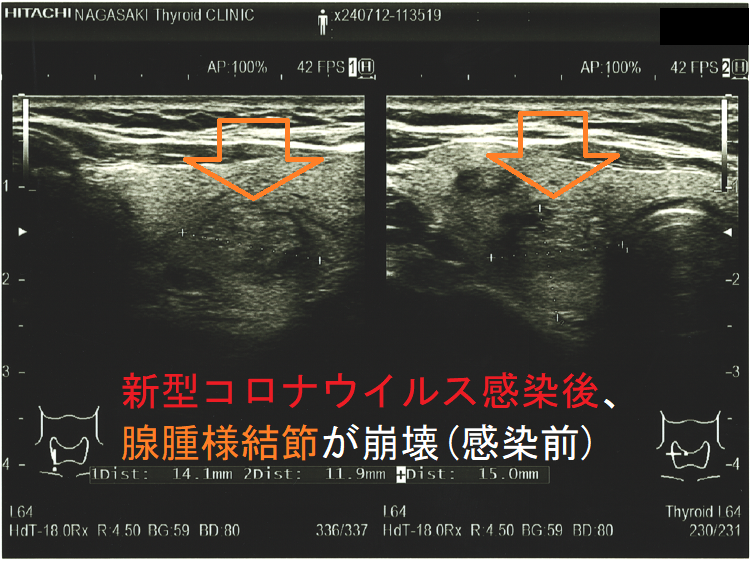

新型コロナウイルス感染(COVID-19)後、腺腫様結節が崩壊(感染後);感染後、内部は崩壊し、亀裂部に液体が充満。のう胞型腺腫様結節(嚢胞型腺腫様結節)のようになってしまった。